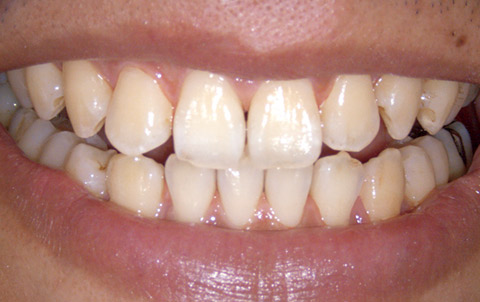

図11 術後の正面観

図12 同、右側頰面観。